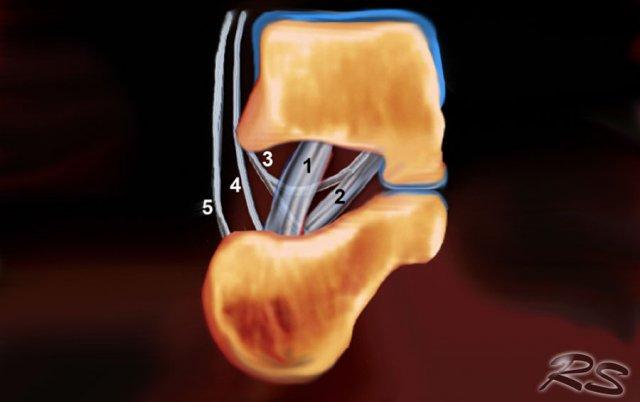

Schematic drawing in a coronal view of the right sinus tarsi. Displayed are the course and attachment sites of the cervical ligament (1); the interosseous talo- calcaneal ligament (2); and the medial (3), intermediate (4), and lateral (5) roots of the inferior extensor retinaculum.

Sinus tarsi

Xoang cổ chân là một khoang hình nón chạy theo hướng từ sau-trong đến trước-ngoài. Nó nằm ở mặt ngoài của bàn chân, giữa cổ xương sên và mặt trên-trước của xương gót.

Xoang cổ chân tiếp nối về phía trong thành ống cổ chân, đây là khoang hình phễu nằm giữa xương sên và xương gót.

Nó chứa mô mỡ, một vòng nối động mạch, bao khớp, các đầu tận thần kinh và năm cấu trúc dây chằng – rễ trong, rễ giữa và rễ ngoài của mạc hãm duỗi dưới; dây chằng cổ; và dây chằng sên gót gian cốt (hình).

Khoang này có thể là nguyên nhân gây đau bàn chân trong hội chứng xoang cổ chân. Bước đầu tiên trong điều trị là tiêm thấm xoang cổ chân bằng hỗn hợp Depomedrol và thuốc gây tê tại chỗ (Lidocaine). Điều này có thể gây khó khăn cho phẫu thuật viên khi thực hiện theo phương pháp không có hướng dẫn, nhưng có thể thực hiện một cách tương đối dễ dàng và chính xác với sự hỗ trợ của siêu âm.

Tiêm dưới hướng dẫn siêu âm vào xoang cổ chân bên phải với đường vào từ phía ngoài. Đầu dò được giữ theo mặt phẳng chếch vành. Kim được đưa vào dọc theo trục dài của đầu dò.

The sinus tarsi can easily be visualized using ultrasound.

Bệnh nhân lăn sang bên đối diện, đặt bàn chân cần điều trị với mặt trong tiếp xúc với mặt bàn, mặt ngoài của bàn chân hướng lên trên.

Đầu dò được giữ theo mặt phẳng chếch vành so với bàn chân.

Xoang cổ chân được xác định là một khoang hình tam giác nằm giữa mỏm trước của xương gót và cổ xương sên.

Đầu kim (mũi tên) được nhìn thấy trong xoang cổ chân hình nón, được giới hạn bởi xương sên (T) và xương gót (C).

Tùy thuộc vào mức độ viêm, có thể có hiện tượng xung huyết trong khoang và có thể thấy các mạch máu xen kẽ, những mạch máu này cần được tránh. Điều này tương đối dễ dàng, đặc biệt khi sử dụng doppler màu